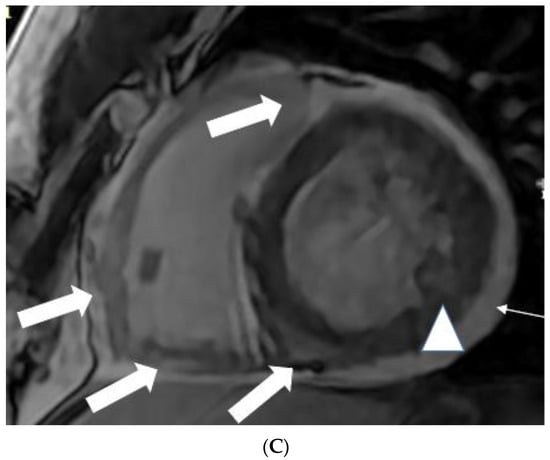

Figure 2.

(A) A 35-year-old male with a recent history of treated tuberculous pericarditis for six months had CMR for ventricular tachycardia. Short axis mid myocardial slice, late enhancement images, shows subepicardial anterolateral (notched arrow), mesocardial mid and inferior septal (white arrow), anterior and posterior RV insertion points (curve arrow) with thickened pericardium and epicardial fat enhancement (thin arrows). Enlarged AL papillary muscle (arrowhead). (B) A 35-year-old male with a recent history of treated tuberculous pericarditis for six months had CMR for ventricular tachycardia. Short axis mid myocardial slice late enhancement images show all the features of (A) and asymmetrical enlargement of the AL papillary muscle (arrow). (C) A 35-year-old male with a recent history of treated tuberculous pericarditis for six months had CMR for ventricular tachycardia. Short axis mid myocardial slice late enhancement images show the RV lateral and inferior wall (arrow), superior and inferior insertion (white arrow) with epicardial fat enhancement (thin arrows). PM papillary muscle is with central enhancement (arrowhead).

Figure 3.

A 35-year-old male with a recent history of treated tuberculous pericarditis for six months had CMR for ventricular tachycardia. 4 CH, late enhancement images, shows RV free wall (epicardial and transmural thin arrows), inferior septal (transmural- thick Arrow), lateral wall LV (transmural-thick arrow), and interatrial septum (thin arrow) enhancement.

5.2. TB Myocarditis

Myocarditis is assumed to involve both ventricles diffusely or, less commonly, the right ventricle alone. In one of the studies with endomyocardial biopsy, biventricular involvement was noted in approximately 70% of patients and alone RV myocarditis in 8% [43]. Myocardial involvement may be identified by aberrant ECG changes, transient localized and global wall motion abnormalities, and increased cardiac enzyme levels. The CMR images of the patient included here (Figure 1, Figure 2, Figure 3 and Figure 4) presented with VT and elevated cardiac enzymes with a clinical diagnosis of myopericarditis. CMR verified all three Lake Louise Consensus Criteria and decreased biventricular ventricular function in the present case. There was a disproportionate LGE in the RV free lateral wall, inferior wall, superior and inferior RV/LV junction, and interatrial septum (Figure 2). It supports the etiopathogenesis of cardiac TB by indicating that the right side is more frequently impacted, most likely due to the proximity of the involved right mediastinal lymph node [7,10,11,12]. Patchy transmural, mesocardial (septal), and epicardial LGE are also seen in the left ventricle (Figure 2A). The regional wall motion abnormality of the inferior septum (Figure 2A) corresponds well with the mesocardial enhancement, and it may represent an area of active inflammation evolving into a chronic scar due to tuberculous infiltration [44]. The accuracy of diagnosing myocarditis was further substantiated by a native T1 map of 1132 ± 178 (Figure 4) and ECV of 25 ± 8%. People with acute chest discomfort may be distinguished from those with acute coronary syndrome or myocarditis using the native T1 and ECV [45]. For identifying and assessing diffuse myocardial fibrosis and edema, native T1 and ECV mapping are more sensitive than LGE [45].